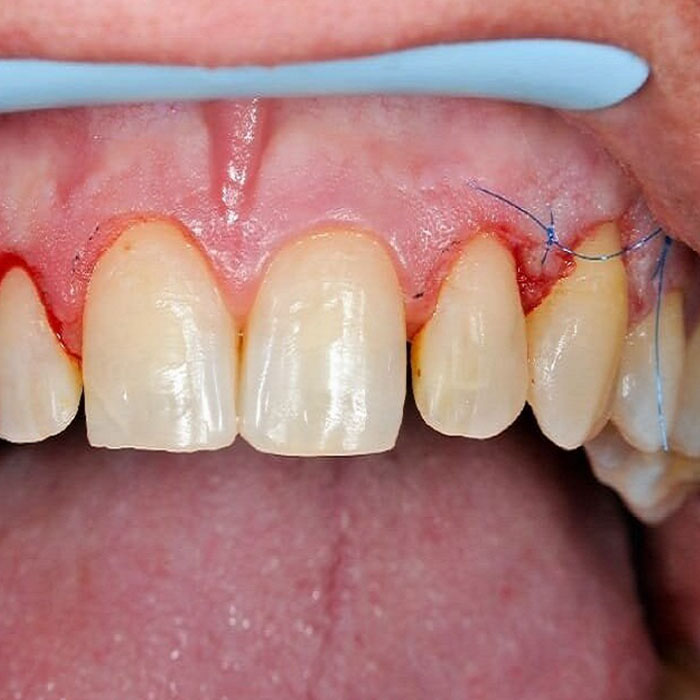

بهترین دکتر جراحی لثه در شیراز + لیست 10 تایی

لثه‌ها به عنوان بخشی مهم از سیستم دندانی بدن نقش بسیار حیاتی…